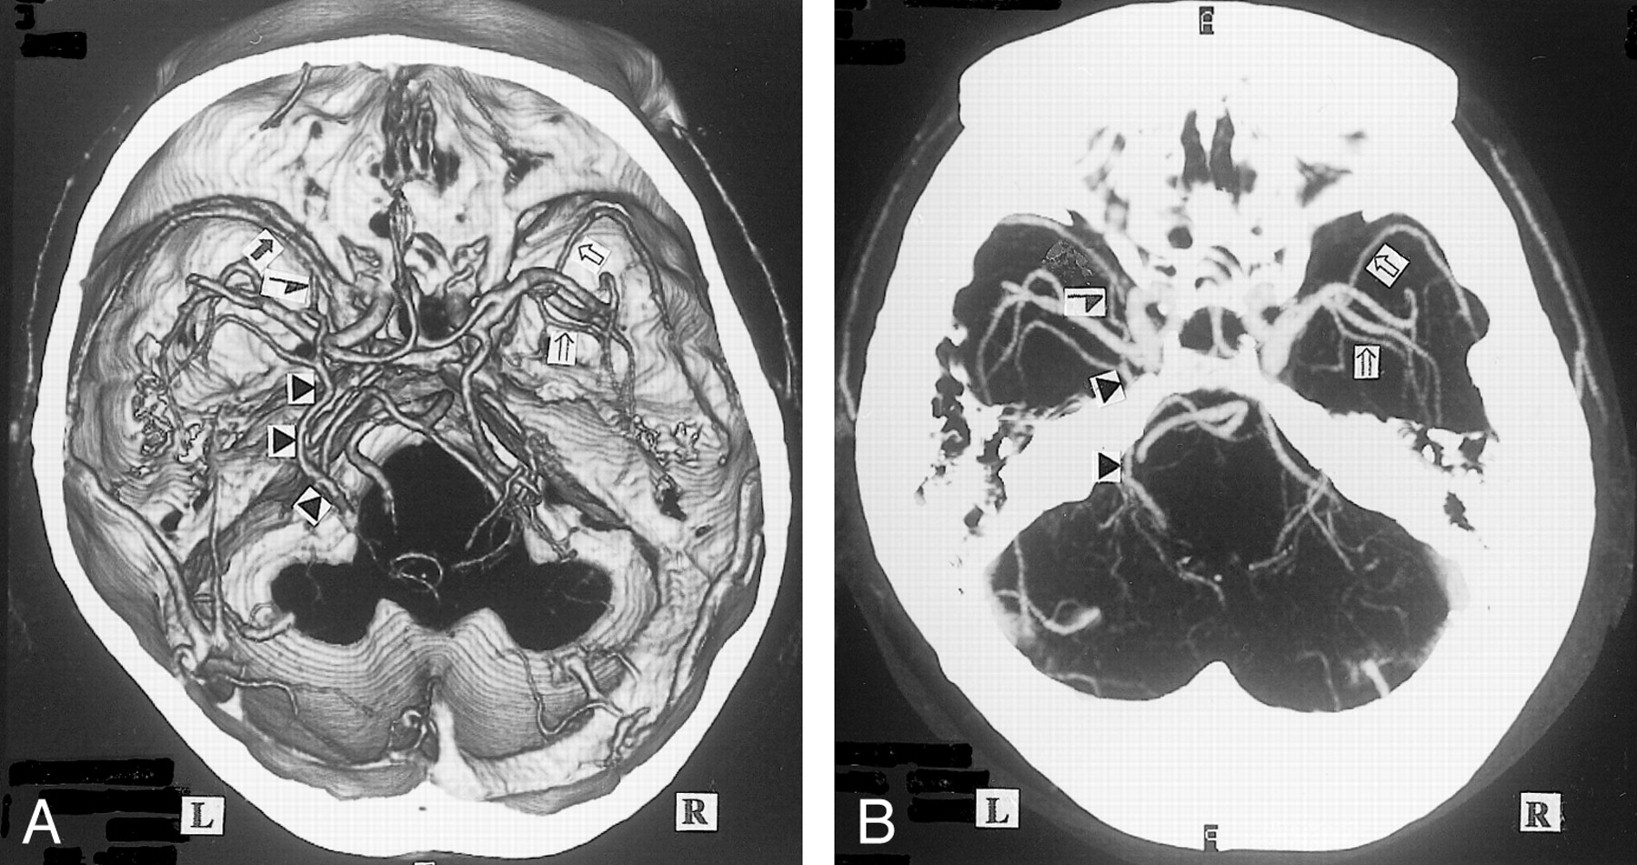

The BVR flowed into the great vein of Galen in 87.8% (Fig 1) , but the anastomoses between the first segment and second segment were not confirmed in 36.9% of this type (Figs 2 and 3; Table 2). The first segments with such hypoplastic or aplastic anastomoses flowed into the cavernous sinus or sphenoparietal sinus. Therefore, typical BVRs with these anastomoses accounted for only 55.4% of all sides. More than one fourth of the typical type also entered anterior sinuses or veins such as the cavernous sinus (Fig 2). Anastomoses between the first segment and the anterior vessels were found in 46.4% of all sides. The hypoplastic anastomosis was only depicted by the MIP image of many sides and appeared aplastic on the 3D CT angiograms (Fig 1). This disparity was also confirmed for the narrow parts of other segments and branches. Many BVRs that flowed into the great vein of Galen also anastomosed with the lateral mesencephalic vein, lateral or medial tentorial sinus, or peduncular vein (Figs 3–5). Other observed drainage patterns included the lateral mesencephalic vein in 5.6% (Fig 6), peduncular vein in 1.6% (Figs 3 and 7), and lateral or medial tentorial sinus in 5.0% (Fig 8). Anterior drainage routes such as the cavernous sinus persisted, not as the main route, but as supplements to the other routes. Many deep middle cerebral veins were identified on the 3D CT angiograms (Figs 3 and 7), but the anterior cerebral veins could not be seen even on the MIP images (Fig 1). The insular vein flowing through the deep middle cerebral vein into the BVR was delineated on many sides (Figs 2 and 3). Some BVRs of the lateral or medial tentorial sinus type coursed at the medial edge of tentorium and flowed into the straight sinus (Fig 8), and others flowed into the transverse sinus through the center or lateral side of the tentorium (Fig 4).

A, 3D CT angiogram (axial view) and B, MIP image. The left BVR (▴) typically courses posteriorly after receiving the deep middle cerebral vein. The anterior cerebral vein cannot be identified (A). The right BVR (▵) is not depicted by 3D CT angiography (A), but is seen by MIP imaging (B)